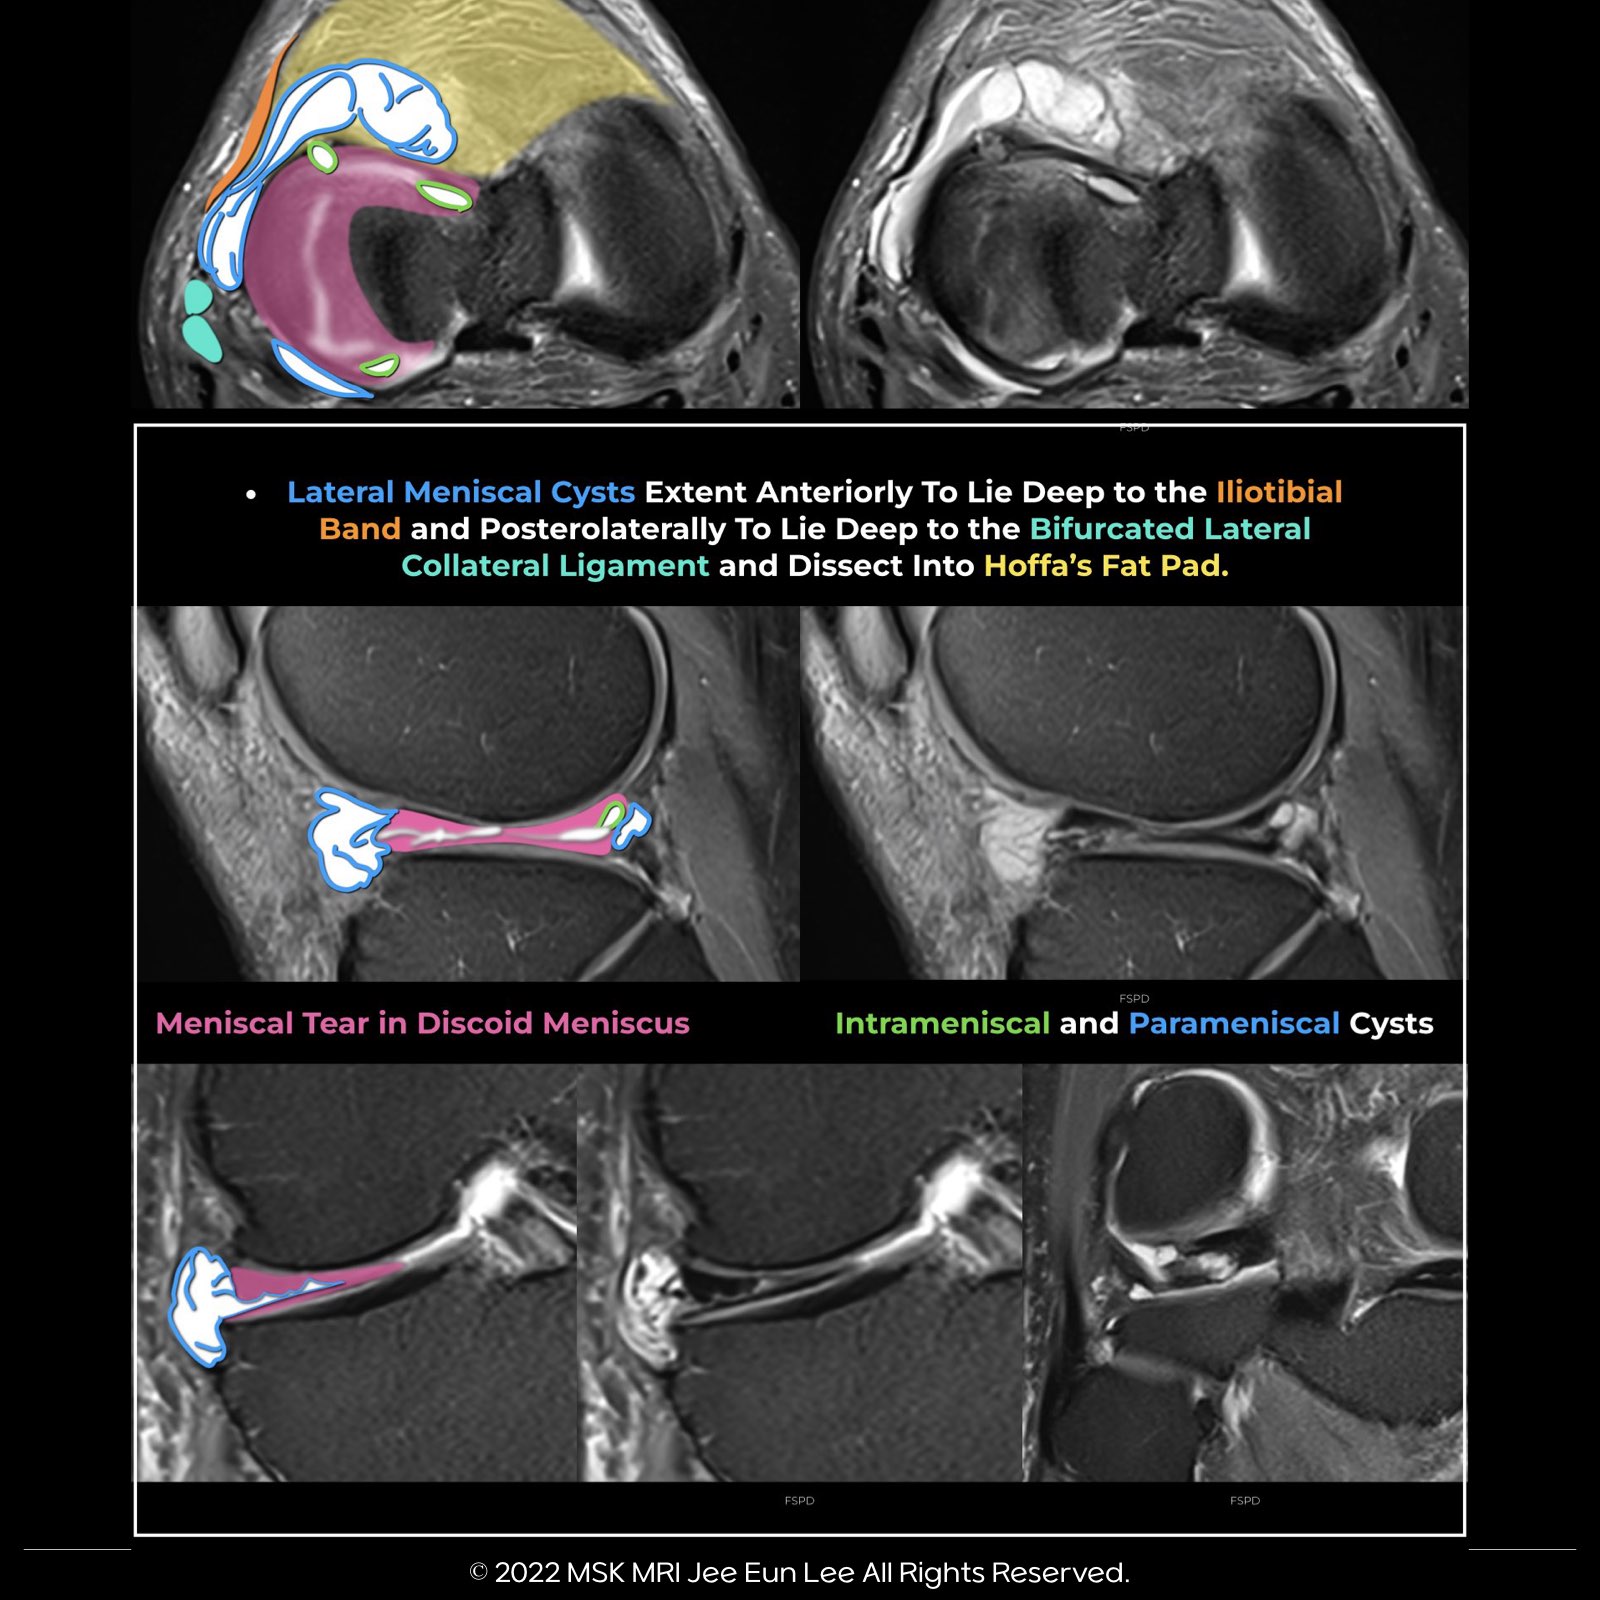

2️⃣ Lateral Meniscal (LM) Parameniscal Cysts

✅ Common Location: Typically found near the anterior horn or the body of the lateral meniscus.

✅ Mobility and Extension: Due to the lateral meniscus's loose attachment to the joint capsule, anterior horn and body cysts can penetrate lateral structures and reach areas deep to the iliotibial tract.

✅ Underlying Tears: In 36% of cases, meniscal tears were not detected in patients with cysts located near the anterior horn or the anterior horn-body regions of the lateral meniscus.

✅ Patterns of Anterior Cysts: These can be located directly in front of the meniscus, dissect into the anterior root, or extend into the Hoffa's fat pad.